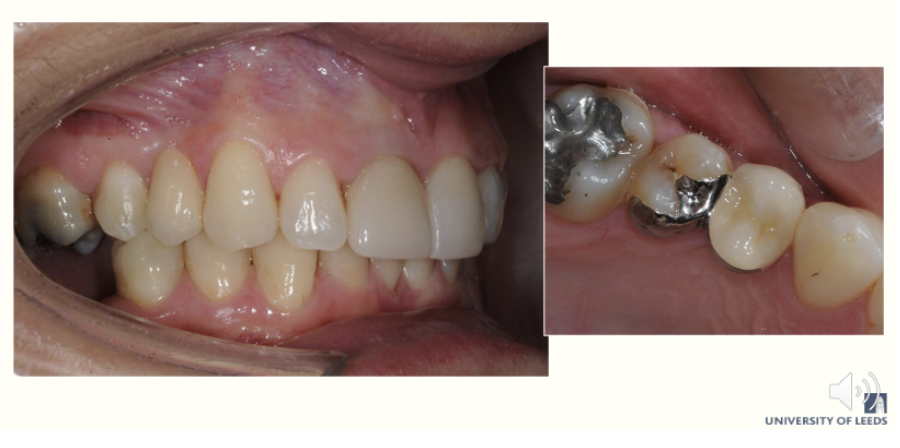

What is the collected Denture

Most common denture - cover whole palate Fully collected denture Popular with dentist and patients Very well tolerated by patients Very retentive and stable

40

What are the limitations of collated dentures

Saliva can't get underneath denture that well Different candida species of fungi can colonise features of denture Candida albicans which lives on inside of denture When mucosa is covered, the saliva can't get underneath and it contains antifungal agents but because saliva can't get underneath the candida thrives

41

why does collecting need to be done correctly

Another problem Collets go Go all around gum margin Denture benign mucosa supported Acrylic is going to be pushing plaque into the pockets all around those teeth all of the time Can lead to inflammation , periodontitis To solve that problem The technician can change the design of the denture so the acrylic goes higher up the tooth the gingival margin Biting force places on tooth than soft tissue